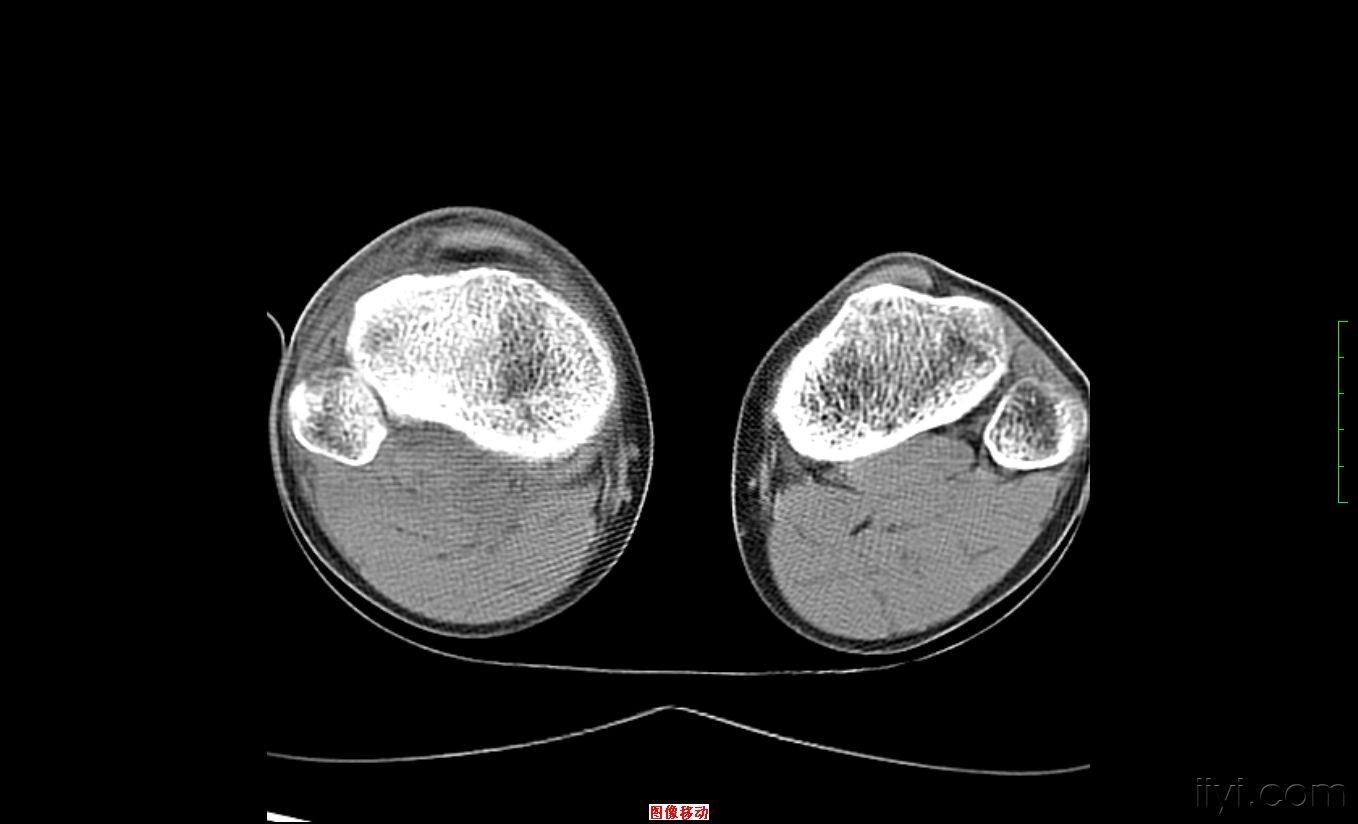

膝盖骨折ct图片,膝盖受伤图片ct拍片图

我院膝关节三维ct可见Ⅴ型胫骨平台骨折,内侧髁骨折无移位,平台无塌陷

术前右膝关节ct

股骨远端骨折(右侧髁上髁间)

膝关节骨折否